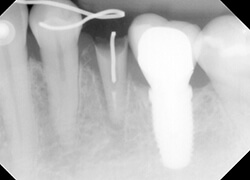

【治療中】

部分矯正で挺出しているところです。歯痕には?マークのようなフックを固定。34(犬歯、第1小臼歯)から伸ばしたワイヤーにリングを設置し、フックからリングを通して、3番(犬歯)のボタンに矯正ゴムを掛けています。

挺出は期間も短く、2週間に一度、ゴムを2回ほど交換して約1か月。